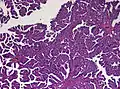

Histopathology

The tumor is neuroectodermal in origin and similar in structure to a normal choroid plexus. They may be created by epithelial cells of the choroid plexus. Papillary fronds lined by bland columnar epithelium are visible under the microscope. Normal absences include mitotic activity, nuclear pleomorphism, and necrosis.[10] Tumors have positive immunohistochemistry for cytokeratin, vimentin, podoplanin, and S-100.[11] Up to 20% of choroid plexus papilloma patients may test positive for glial fibrillary acidic protein (GFAP).[12] Studies have found that fourth ventricle cancers express more S100 than lateral ventricle tumors, and older patients (over 20 years) express more GFAP and transthyretin than younger patients.[13] Some individuals with choroid plexus papilloma have germline TP53 gene mutations, according to genetic analyses.[14] These cancers rarely exhibit nuclear p53 protein positivity. Aicardi syndrome, hypomelanosis of Ito, and 9p duplication are syndromic correlations of choroid plexus papilloma.

Micrograph of a choroid plexus papilloma. H&E stain.

Plexuspapillom Detail

Plexuspapillom Overview